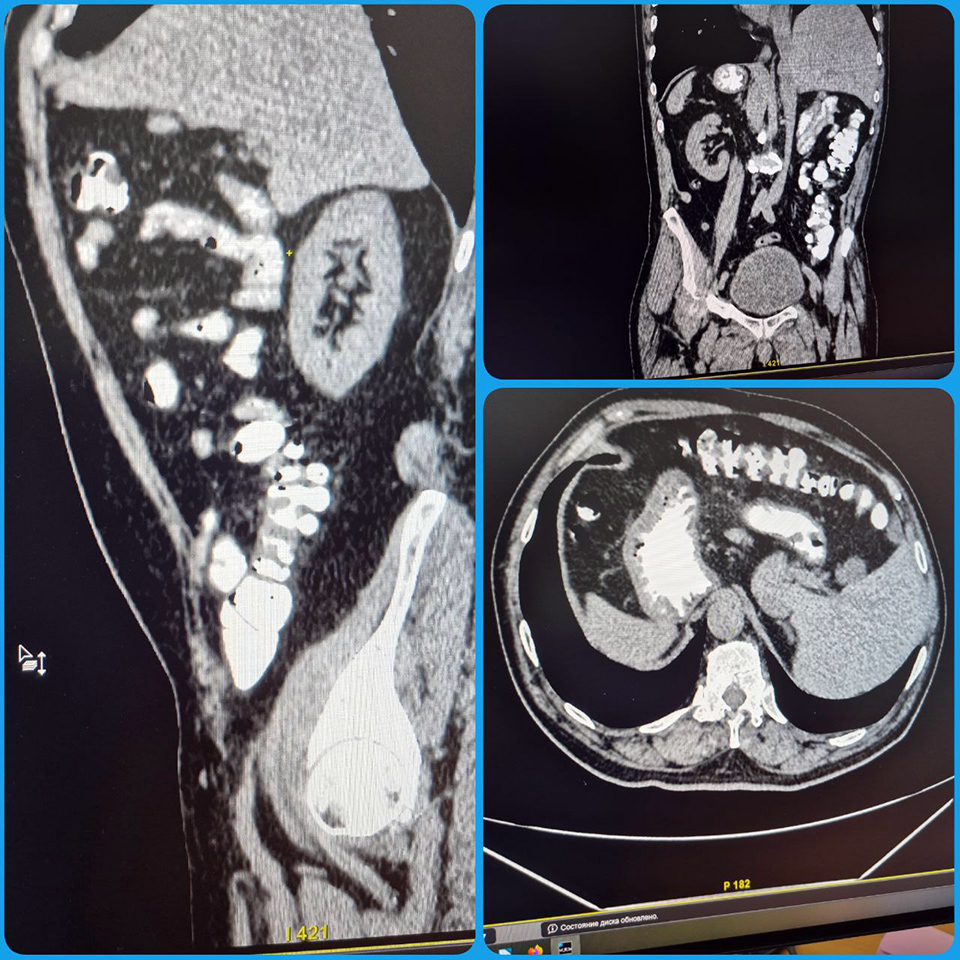

Специалисты Балаковской городской клинической больницы (БГКБ) во время планового КТ-обследования брюшной полости пациента сделали удивительное открытие. Оказалось, что все его внутренние органы расположены… зеркально!

Печень – слева, сердце – справа, аорта и легкие также имеют обратное расположение. Это редчайший случай полной транспозиции органов – врожденной аномалии, при которой тело человека словно отражено в зеркале.

Как сообщает телеграм-канал БГКБ, мужчина, проходивший обследование, не знал о своей особенности. Такая анатомия не влияет на самочувствие и обнаруживается, как правило, случайно – во время диагностики по другим причинам.

– Это первый подобный случай за 10 лет моей практики, – отметила Елена Магомедова, и.о. заведующего рентгенологическим отделением БГКБ. – Полная транспозиция органов – крайне редкое явление, настоящая медицинская редкость.